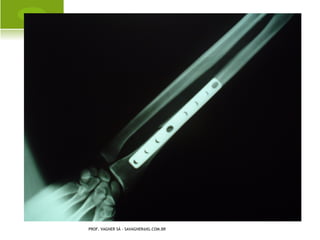

F RATURA -L UXAÇÃO

G ALEAZZI